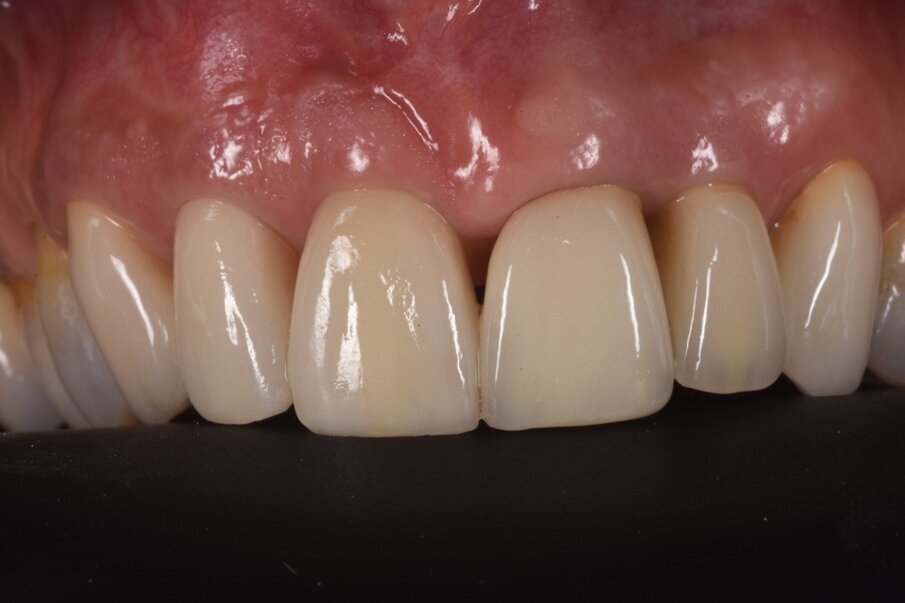

La finalizzazione del caso ha previsto poi il rifacimento della vecchia corona su 12 insieme a quella su 11 in zirconia stratificata, progettata con il CAD/CAM, favorendo così il ripristino della funzione e dell’estetica laddove una complicanza aveva compromesso il risultato ottenuto dieci anni prima (Figg. 17-19). Sei mesi dopo l’intervento si può ben vedere come clinicamente e radiologicamente si sia ottenuto un buon successo bilogico ed estetico (Figg. 20-22).